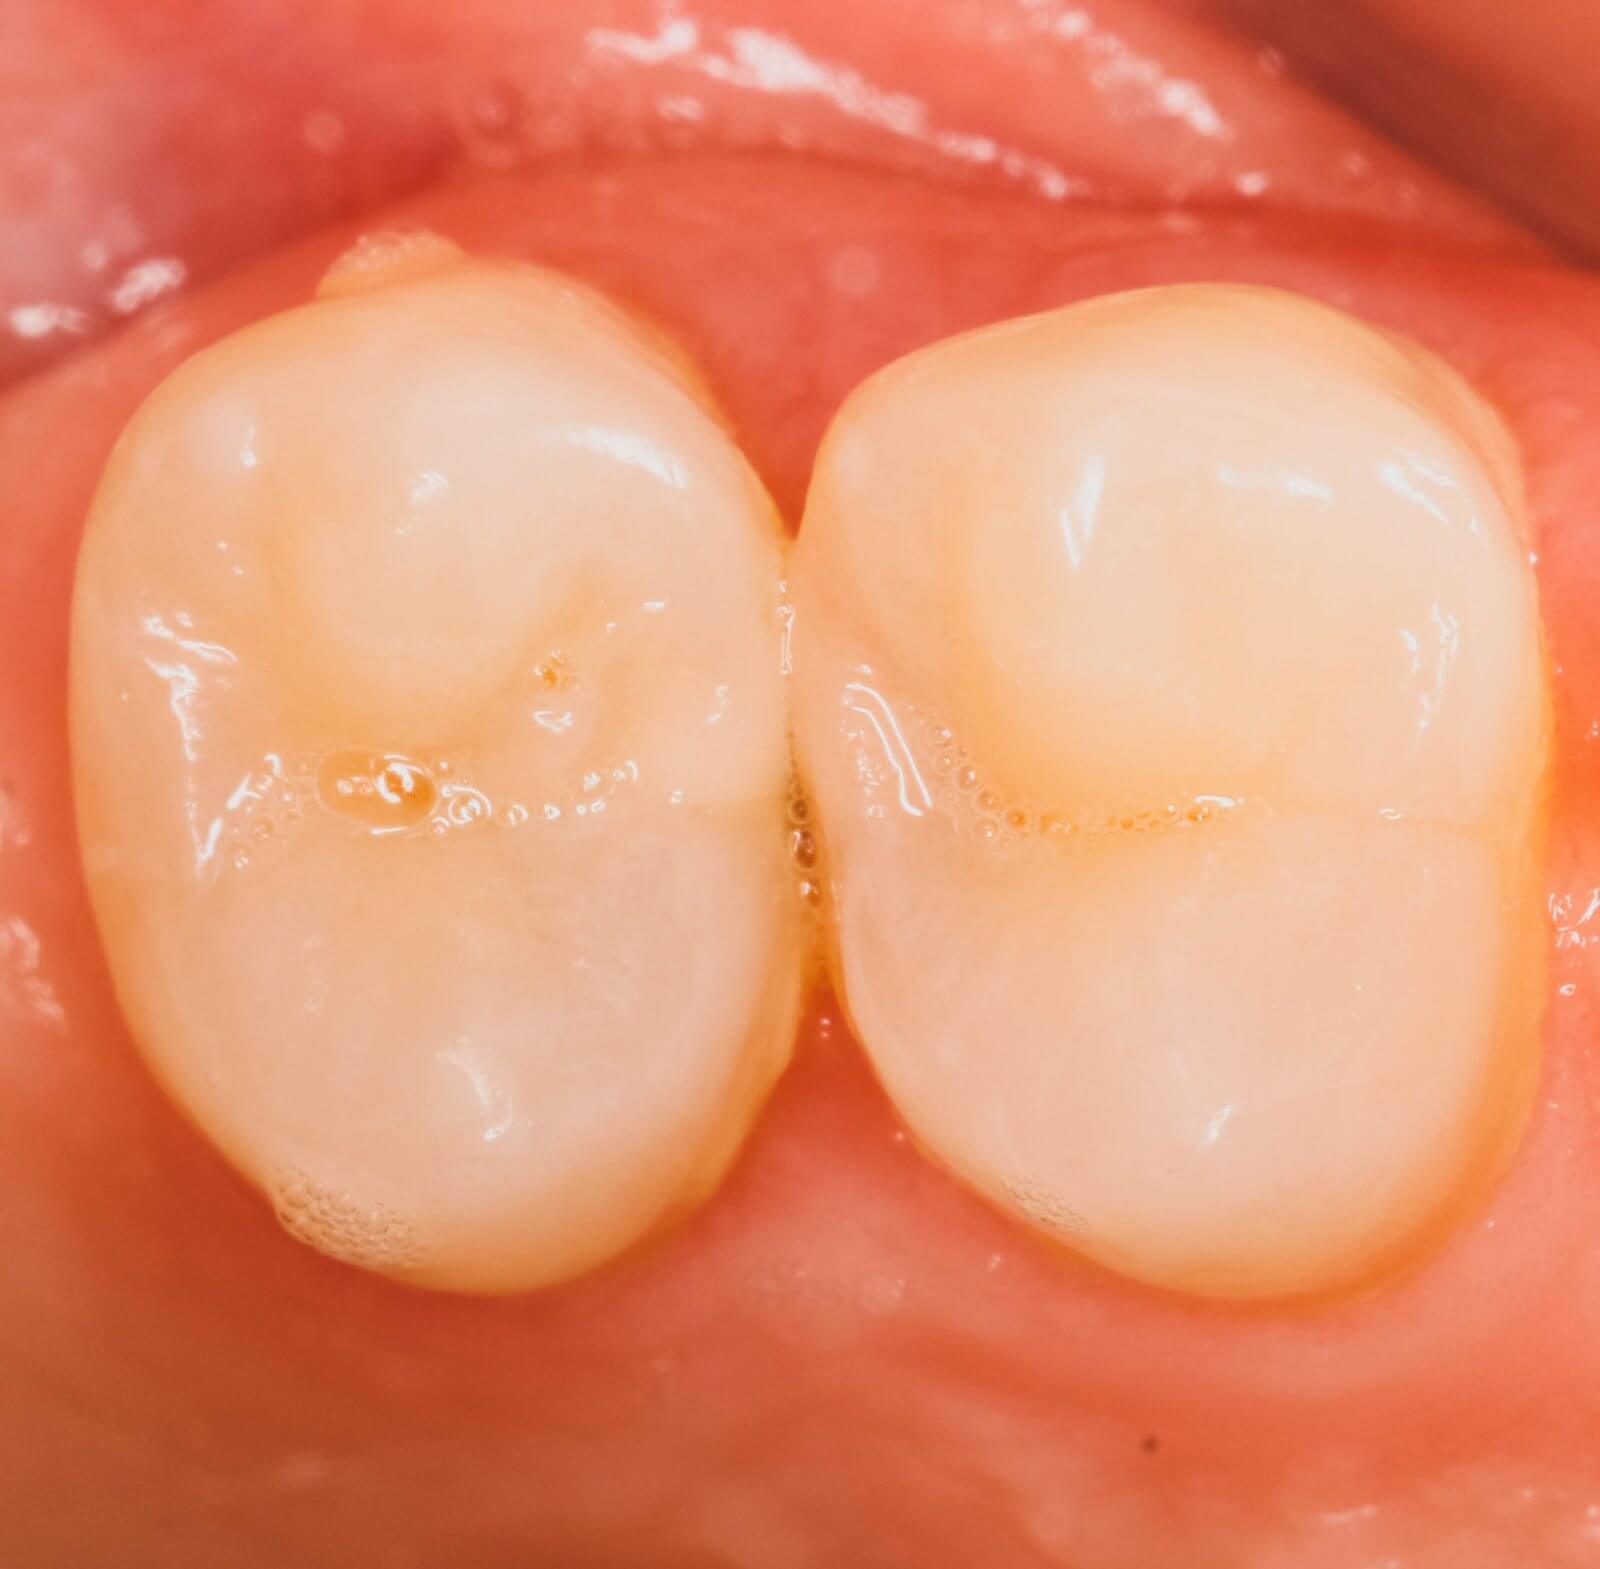

Скрытые кариозные полости (кариес на боковой поверхности) считаются самыми коварными в практике стоматолога-терапевта. В ранней (неосложненной) стадии они плохо диагностируются из-за недостаточного освещения и увеличения, что в совокупности с «классической» методикой препарирования через жевательную поверхность приводит к большому и ненужному удалению твердых тканей зуба. А это большая потеря для последнего. |

| Лечение зубов под микроскопом дает врачу огромное увеличение от 10х до 25х, а также качественный свет до 100 тыс. люкс (прямые солнечные лучи в тропиках). Это позволяет врачу раньше найти проблему и убрать только плохие инфицированные ткани зуба, максимально сохраняя здоровые. Так, в следующем клиническом случае мы под микроскопом (10х увеличение!) нашли скрытый кариес между зубами 2.4/2.5 (рис. 2). |

Кариозные полости мы подготовили в современной концепции «минимально-инвазивного препарирования, что возможно только с большим увеличением и освещением (рис. 3 и 4).